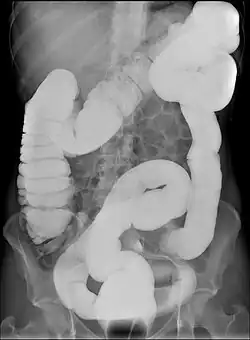

Dolichokolie ist eine abnorme Länge des Grimmdarms bei normalem Durchmesser (Synonym: Dolichokolon, auch Colon elongatum und Sigma elongatum). Dolichokolie diagnostizierte man früher häufig als Ursache für chronische Verstopfung und riet dann, den Grimmdarm operativ zu kürzen. Dies wird heute allgemein als Fehlschluss angesehen.